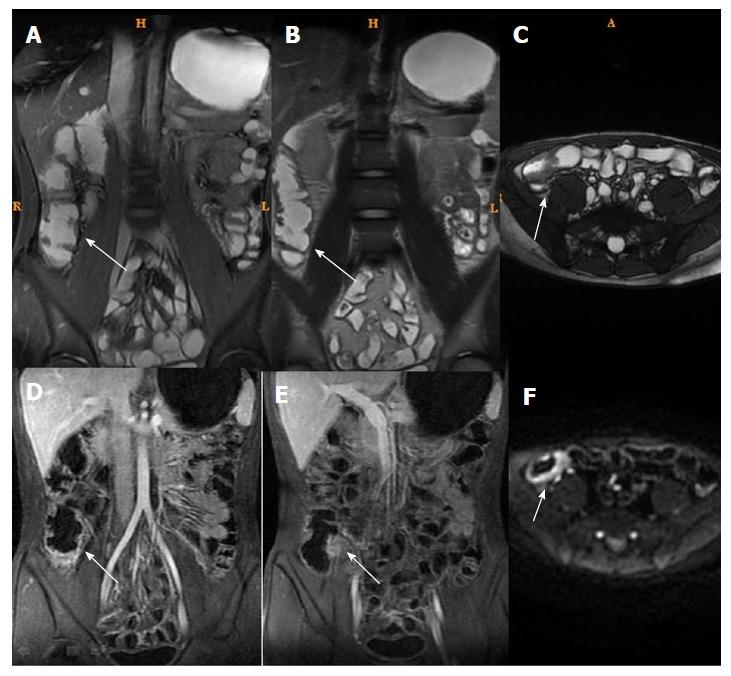

磁共振成像与克罗恩病内镜严重程度指数:相关性和一致性。

Magnetic resonance imaging and Crohn's disease endoscopic index of severity: Correlations and concordance.

To examine the correlation between magnetic resonance imaging (MRI) and endoscopic index of severity (CDEIS) in patients with Crohn's disease (CD).

METHODS

This was a retrospective study of 104 patients with CD that were treated at the Ruijin Hospital between March 2015 and May 2016. Among them, 61 patients with active CD were evaluated before/after treatment. MRI and endoscopy were performed within 7 d. CDEIS was evaluated. MRI parameters included MaRIA scores, total relative contrast enhancement (tRCE), arterial RCE (aRCE), portal RCE (pRCE), delay phase RCE (dRCE), and apparent diffusion coefficient. The correlation and concordance between multiple MRI findings and CDEIS changes before and after CD treatment were examined.

RESULTS

Among the 104 patients, 61 patients were classified as active CD and 43 patients as inactive CD. Gender, age, disease duration, and disease location were not significantly different between the two groups (all > 0.05). CRP levels were higher in the active group than in the inactive group (25.12 ± 4.12 5.14 ± 0.98 mg/L, < 0.001). Before treatment, the correlations between CDEIS and MaRIAs in all patients were = 0.772 for tRCE, = 0.754 for aRCE, = 0.738 for pRCE, and = 0.712 for dRCE (all MaRIAs, < 0.001), followed by MRI single indexes. Among the active CD patients, 44 cases were remitted to inactive CD after treatment. The correlations between CDEIS and MaRIAs were = 0.712 for aRCE, = 0.705 for tRCE, = 0.685 for pRCE, and = 0.634 for dRCE (all MaRIAs, < 0.001).

CONCLUSION

Arterial MaRIA should be an indicator for CD follow-up and dynamic assessment. CD treatment assessment was not completely concordant between CDEIS and MRI.